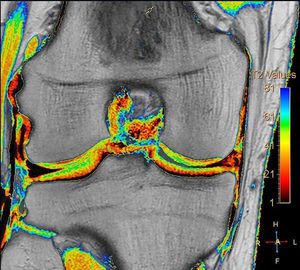

Figure shows T2 mapping of the knee articular cartilage, courtesy of Philips Medical Systems. Note that deeper layers near the bone have shorter T2 values (orange). Trauma, degeneration, and inflammatory changes in articular cartilage are generally manifest by increased free water content and loss of proteoglycans, causing increased T2 relaxation times.